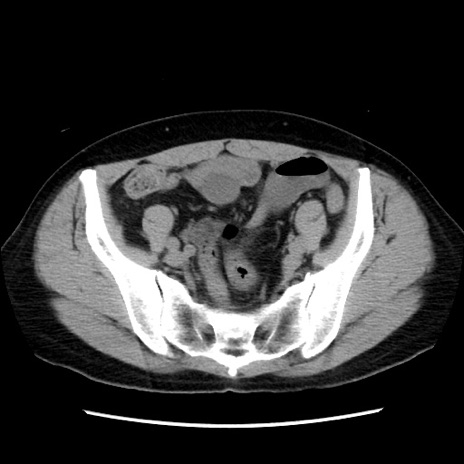

症例10(横断像)

【症例】 50歳代女性

【主訴】 腹痛

【現病歴】前日生レバーを食べた。今朝に排便あり。 昼前に突然発症の腹痛を生じ、当院救急外来を受診した。

【既往歴】 子宮筋腫にてで子宮全摘後

【身体所見】 意識清明、腹部:平坦、軟、下腹部やや左を中心に圧痛・反跳痛あり、筋性防御あり

【データ】WBC 7800、CRP 0.07